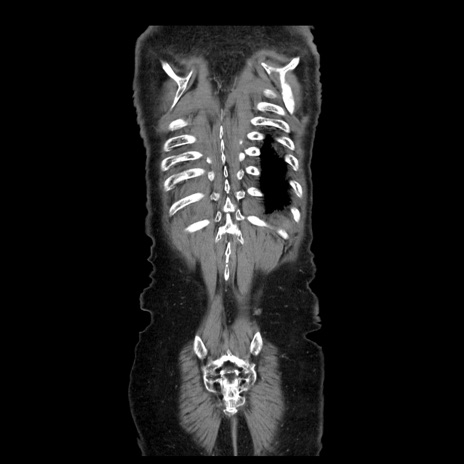

症例21(冠状断像)

【症例】70歳代男性

【主訴】腹痛

【現病歴】肝硬変・肝細胞癌にてかかりつけの方。約9時間前に食後より腹痛出現。症状が徐々に増悪し、嘔吐出現したため来院。

【既往歴】肝硬変、肝細胞癌(RFA、TACE後)

【身体所見】意識清明、表情苦悶様、BT 36℃、BP 129/78mmHg、P 88bpm、SpO2 97%(RA)、右上腹部から心窩部にかけて圧痛あり、反跳痛なし、筋性防御あり。

【データ】WBC 5800、CRP 0.16